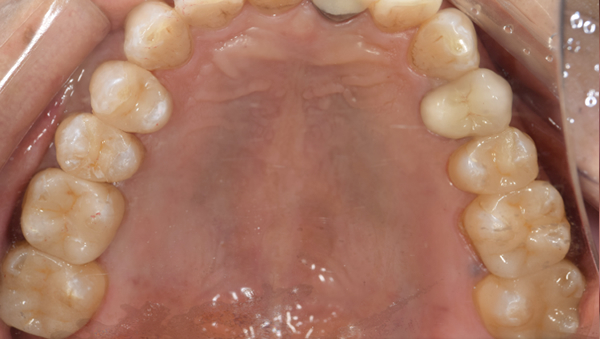

治療前

治療後

治療内容

口腔内の銀歯を全てセラミックにしたいというご希望でした。親知らずは抜歯しています。笑ったときや自然なスマイルをしたときも銀歯が見えなくなり自然になりました。

治療期間 約2ヶ月

治療費 合計:935,000円 (内訳)

オールセラミック:110,000円×5本

セラミックインレー:55,000円×7本

治療のリスク・副作用 銀歯の下で虫歯が大きくなっていたら歯の中の神経をとらないといけないことがあります。また、被せ物を外すと、ご自身の歯が少ない場合は別途はを残すための処置が必要になることがあります。